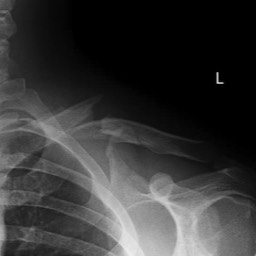

A 15 year old female fell from her pushbike causing a displaced left mid-shaft clavicular fracture. Seen 5 days later, plate & screws inserted 2 days later.

Image

DIsplaced fracture before surgery

DIsplaced fracture after surgery

Move the slider to compare before surgery and after surgery